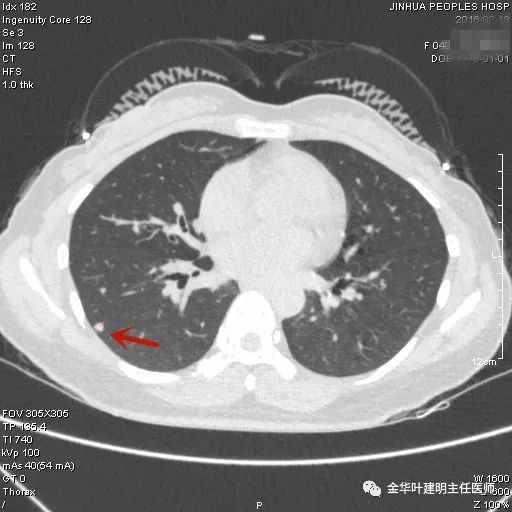

上图示胶原结节。我的理解是较慢性炎更向纤维瘢痕钙化发展,但仍未达钙化程度的一种状态(我不知道病理是不是这样)。该病灶表现为小而密度高的结节,边缘清晰,邻近胸膜却不牵拉,没有收缩力。